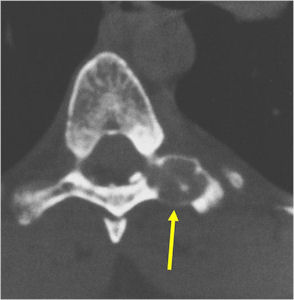

Radiographic imaging is used to help form a diagnosis. These include X-Ray, MRI, CT and Bone Scans.

An example of an CT is shown.